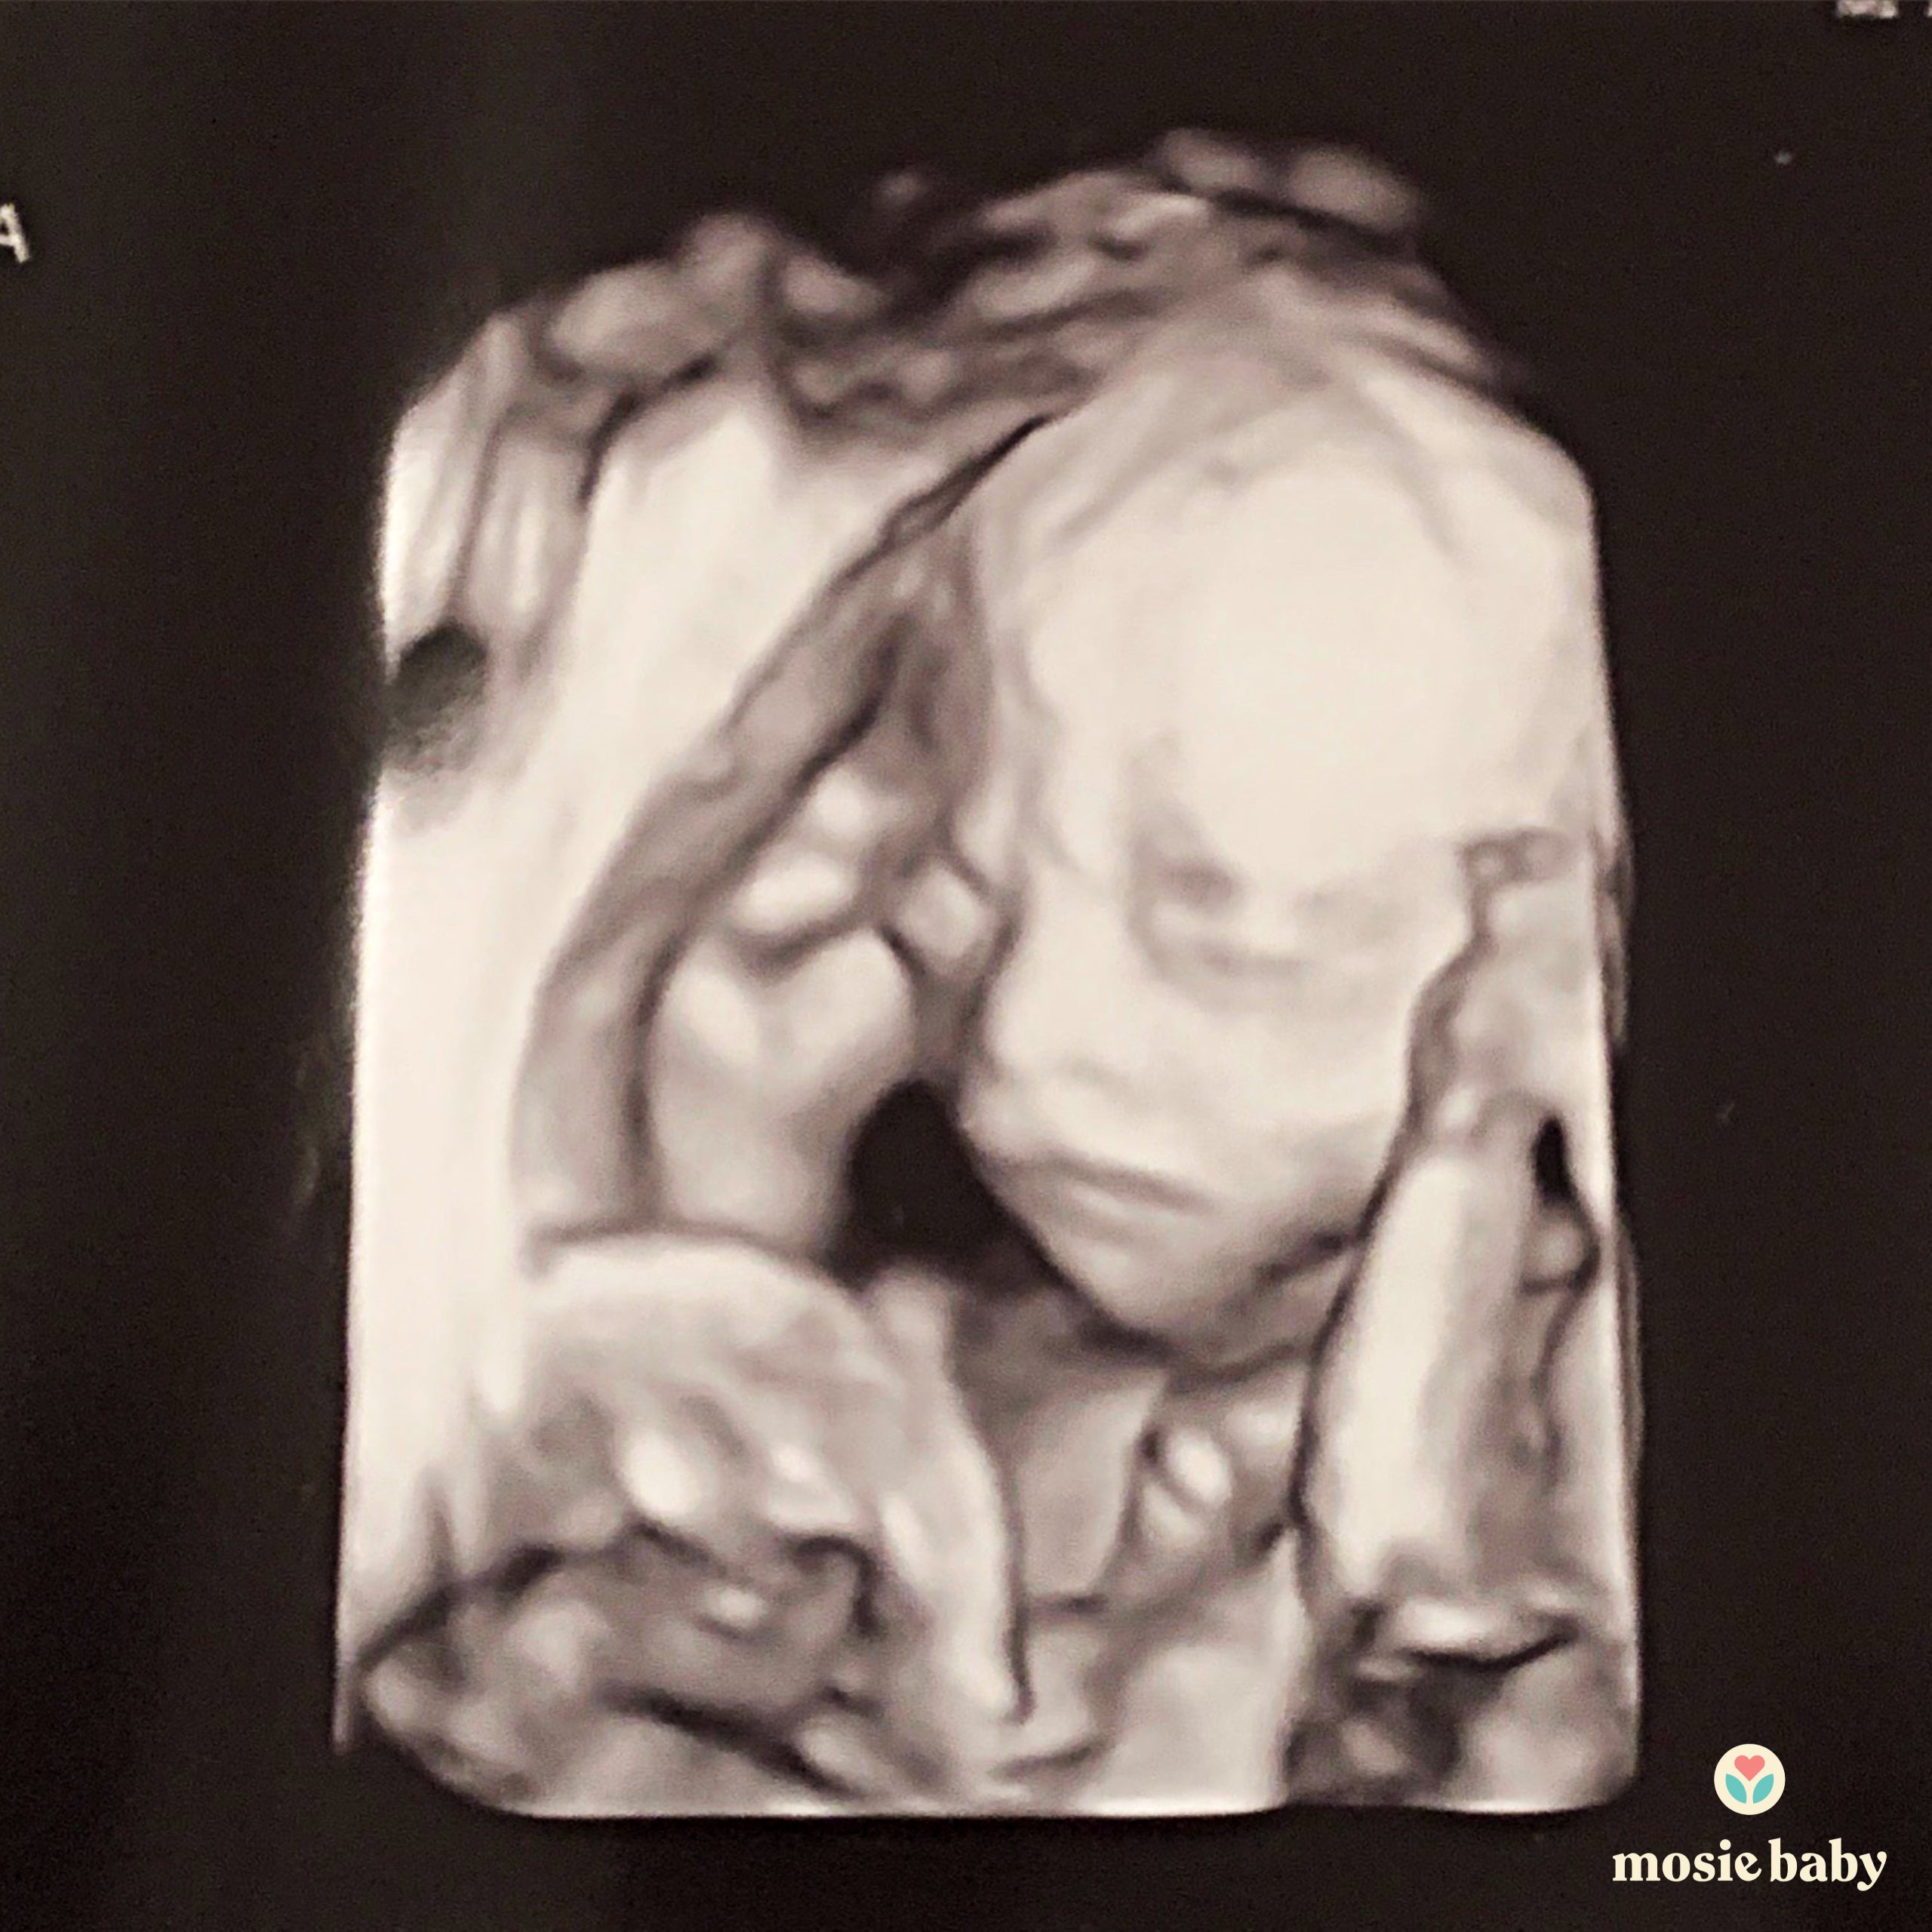

I told my husband straight away, and we were overjoyed! A few weeks later when we went for our first scan we found out we were having twins! I am now happy to report that we are almost in the third trimester and eagerly waiting for our twin girls to arrive!